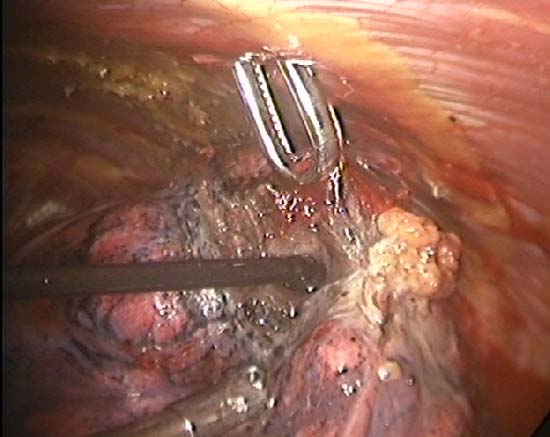

The TissueLink device does not perforate or cut into tissue (in contrast to conventional electrocautery). Instead, the surface of the tissue is painted with the device, which first coagulates and then shrinks the lung tissue (Figure 3). The surgeon then divides the coagulated tissue with scissors (Figure 4). Compared with conventional electrocautery, the TissueLink device usually leaves the resection bed more hemostatic and pneumostatic.